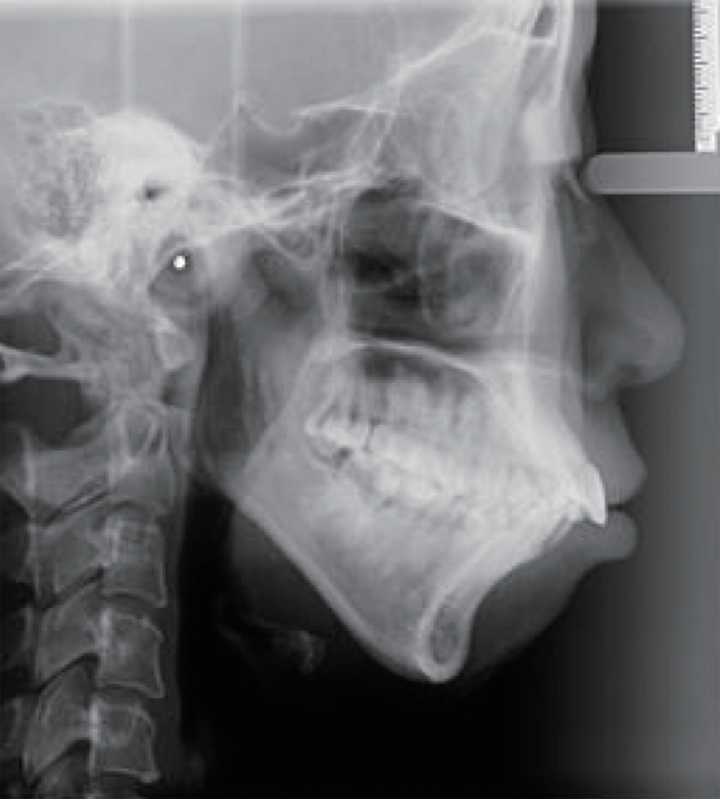

矫正行动:如果评估确认存在下颌后缩且适合功能矫治,如果是高角下颌后缩,可以考虑Twin-block,头帽肌激动器,均角低角下颌后缩可以考虑斜导,还有无托槽隐形矫治、II类牵引、Grace个性化硅胶矫治器等。对于牙弓狭窄的情况,可以考虑扩弓装置,解除锁结关系,为下颌前伸提供空间。

矫正效果:这些矫治器通过改变口周肌肉的力量和下颌的位置,限制上颌的过度生长,从而达到协调上下颌骨关系、促进下颌发育的目的。在这个生长高峰期进行干预,孩子不用拔牙,且早期矫正效果事半功倍!